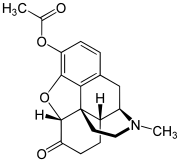

3,6-diesters of morphine

- Acetylpropionylmorphine

- 3,6-Dibutanoylmorphine

- Diacetyldihydromorphine (dihydroheroin, acetylmorphinol)

- Dibutyrylmorphine

- Dibenzoylmorphine (first designer drug)

- Diformylmorphine

- Dipropanoylmorphine

- Heroin (diacetylmorphine)

- Nicomorphine

Structures

| 3,6-diesters of morphine | ||||

|---|---|---|---|---|

Acetylpropionylmorphine Acetylpropionylmorphine |

3,6-Dibutanoylmorphine |  Diacetyldihydromorphine Diacetyldihydromorphine(dihydroheroin, acetylmorphinol) | ||

Dibutyrylmorphine Dibutyrylmorphine |

Dibenzoylmorphine Dibenzoylmorphine |

Diformylmorphine Diformylmorphine | ||

Dipropanoylmorphine Dipropanoylmorphine |

Heroin Heroin(diacetylmorphine) |

Nicomorphine Nicomorphine | ||